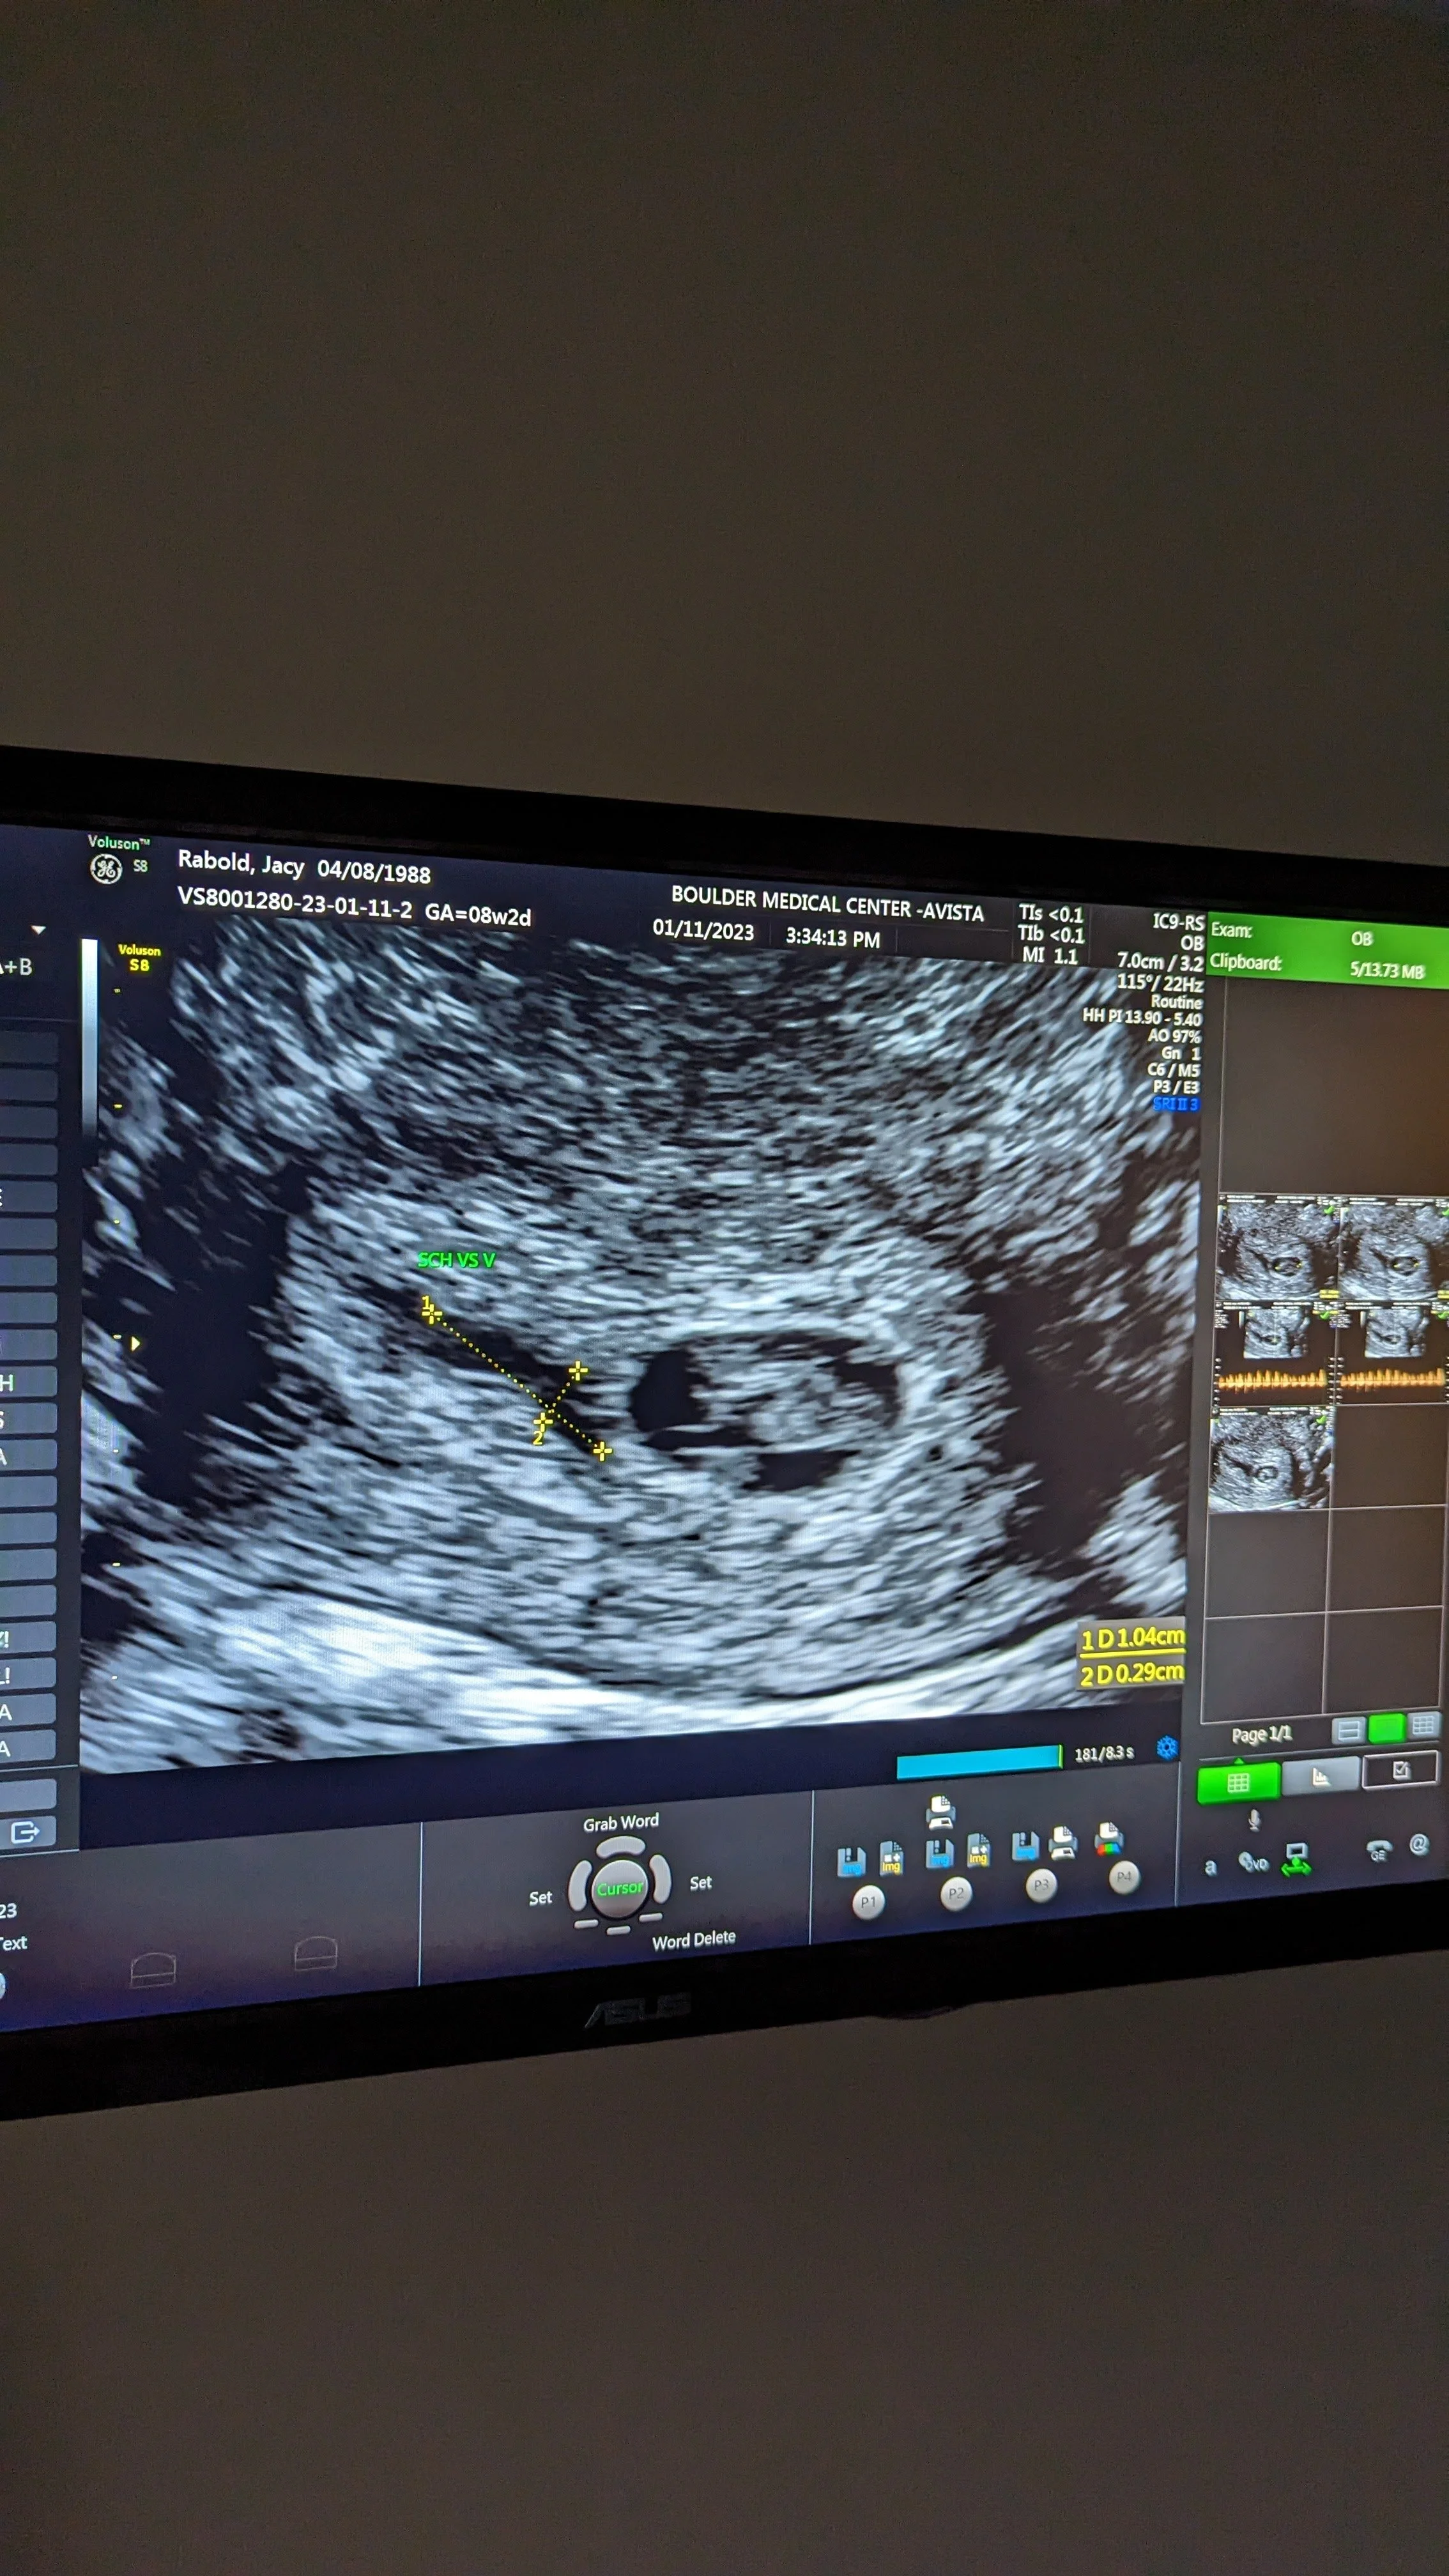

The holidays passed, and January came, and we got our official confirmation of pregnancy. A strong heartbeat at 161 beats/minute. We left the appointment feeling hopeful.

On Tuesday night, I had some red flags that gave me enough of a pause to text my old Austin OB and see if she could get me first thing the next day. The next morning at the doctor's, it was immediately clear that the strong heartbeat I had seen a week prior was no longer so obvious. The doctor said she couldn’t see anything, but wanted to bring in a specialized ultrasound tech to confirm.

She confirmed what I already knew in my heart.

There was no heartbeat; I was experiencing a miscarriage.